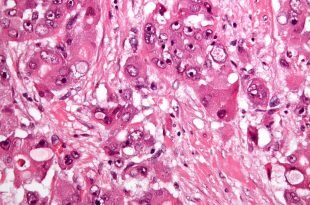

Злокачественные образования и метастазы печени

Когда в тканях печени происходит аномальное деление клеток, отличных от типа структур органа, диагностируют злокачественную опухоль. Чаще такое формация является результатом метастазирования рака другой системы. Различают 4 стадии патологии. Первые две сложно выявить из-за бессимптомности или маскировки под обычные болезни. Специфика ранней картины — желудочные расстройства (тошнота, рвота, потеря аппетита, жар), желтуха и зуд кожи, позже добавляется асцит. Поздними симптомами являются признаки отравления организма. Лечение хирургическое с химиотерапией и облучением.